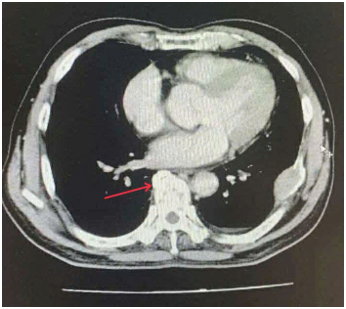

Case lâm sàng: Ứng dụng trí tuệ nhân tạo (Artificial intelligence – AI) trong chẩn đoán và điều trị sớm Ung thư phổi tại Trung tâm Y học hạt nhân và Ung bướu, Bệnh viện Bạch Mai

Theo GLOBOCAN 2022, ung thư phổi đứng đầu về số ca mới mắc (2.480.301 ca mới mắc chiểm 12.4%) và dẫn đầu số ca tử vong (1.817.172 ca tử vong chiếm 18.7%) trên toàn thế giới.  Tại Việt Nam tỷ lệ mắc ung thư phổi xếp thứ ba 13,5% lệ tử vong...